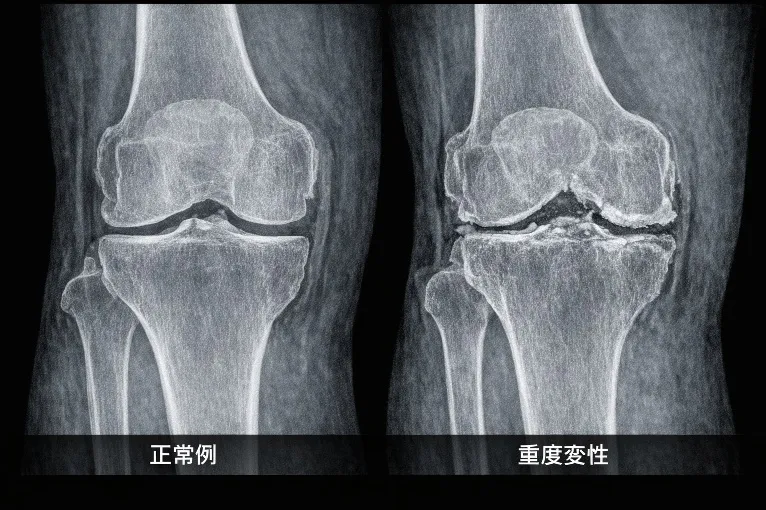

◆レントゲンより詳しく分かる

・骨の変形、骨折

・関節のすり減り